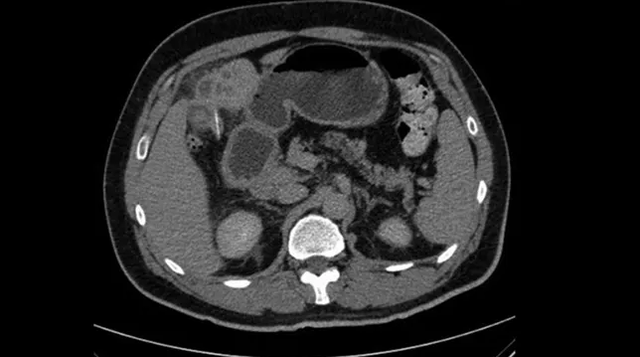

Dokter lantas melakukan rontgen perut, tapi tidak menemukan adanya tanda-tanda yang aneh. Pemindaian computed tomography (CT) pada perut menunjukkan bahwa ginjal, limpa, pankreas, dan kantung empedu tampak normal.

Ketika tim medis memeriksa bagian tengah hati pasien, mereka menemukan dua kelainan. Pertama adalah lesi yang tampak seperti abses, dan yang kedua adalah benda padat seperti ranting di dalam lesi tersebut dengan ukuran panjang sekitar 2,5 centimeter.